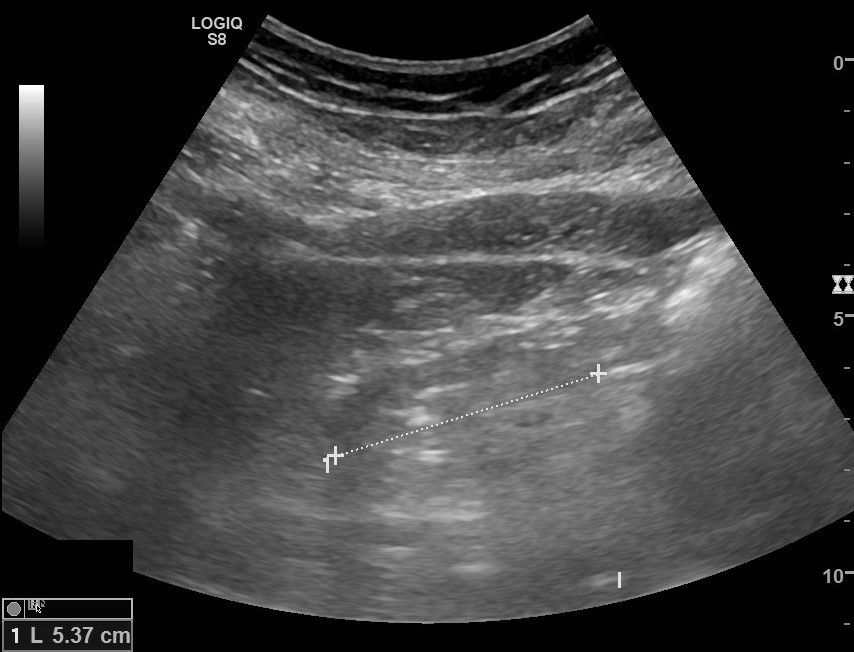

Ante hipertensión arterial (HTA) mal controlada a pesar de tres fármacos, y empeoramiento de la función renal, se realiza diagnóstico de HTA resistente y se realiza ecografía clínica en consulta de AP, donde se objetiva imagen hipoecogénica ovalada paraesplénica 5.3cm, sospechando atrofia renal izquierda; con riñón derecho conservado.

Se solicita ecografía urológica, la cual confirma la atrofia renal.